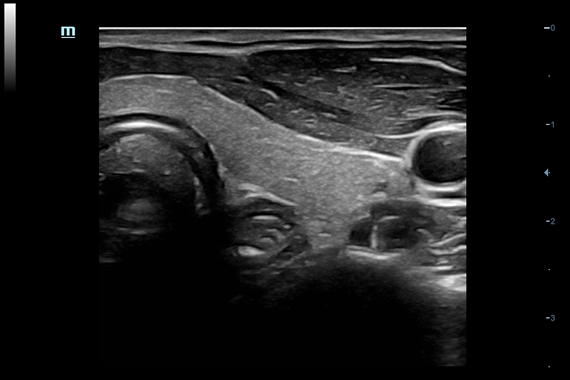

Система ультразвукового исследования Mindray DC-60 EXP X-INSIGHT является новейшей разработкой для проведения комплексных обследований на высшем уровне. Она обеспечивает решение самых сложных задач в таких областях, как кардиология, акушерство и гинекология, сосудистые заболевания, педиатрия и многие другие.

DC-60 EXP X-INSIGHT - это современный стационарный УЗИ-аппарат с функцией сенсорного управления и очищенной гармонической визуализацией, обеспечивающей лучшее контрастное разрешение и технологию 4D-визуализации. Он оснащен 21,5-дюймовым монитором, который может поворачиваться на 180 градусов, что удовлетворяет потребности врачей в качественной ультразвуковой диагностике.

• Поддержка режимов сканирования B/M/Цветовой доплер CDI/Цветной M/Энергетический доплер PD/Направленный энергетический доплер Dir.PD.